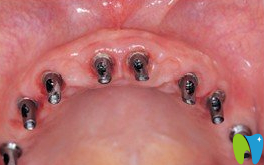

登特口腔種植牙術(shù)中

登特口腔的醫(yī)生護(hù)士都很負(fù)責(zé),定期打電話做復(fù)診以及其他的種植手術(shù)療程。自從做完了種植牙之后,胃口大增,吃的也變多了。我就知道這顆種植牙做的很值,價格不貴,效果還好,以前吃飯都很艱難的我,現(xiàn)在吃飯居然快趕上年輕人的速度了,這真的要感謝盧偉院長的好技術(shù)!